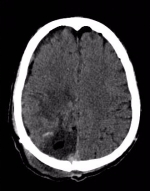

△术后头颅CT显示畸形团切除彻底

手术团队奋战8小时,终于在少量出血的情况下完整切除脑动脉畸形,并清除颅内血肿。